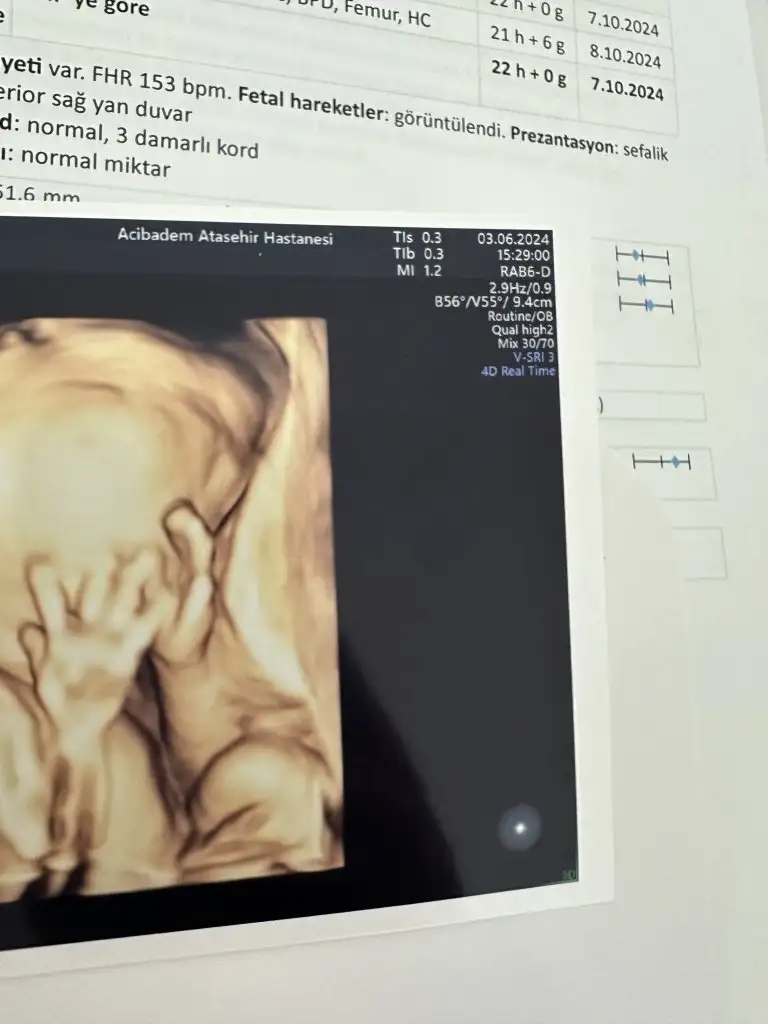

Süper ya çok sevindim görmenize🤗 detaylı için başka doktora gittim hoca işinde çok iyiydi gerçekten hem fetal eko hem detaylıyı yaptı.. amaa bizimle iletişimi çok azdı😕 acıbadem ataşehir e gittim kendi doktorum da orda olduğu için direk bu hocaya yönlendirdi..3. Bebeğim olduğu için biliyorum sonuçta, hiç bi sorun çıkmamasına rağmen (çok şükür) çok gergindim ben hocanın iletişimsizliği hiç hoşuma gitmedi, belki de çok önemsemedi güzel poz yakalamayı filan 😂 ayy iyii oldu içimi döktüm valla